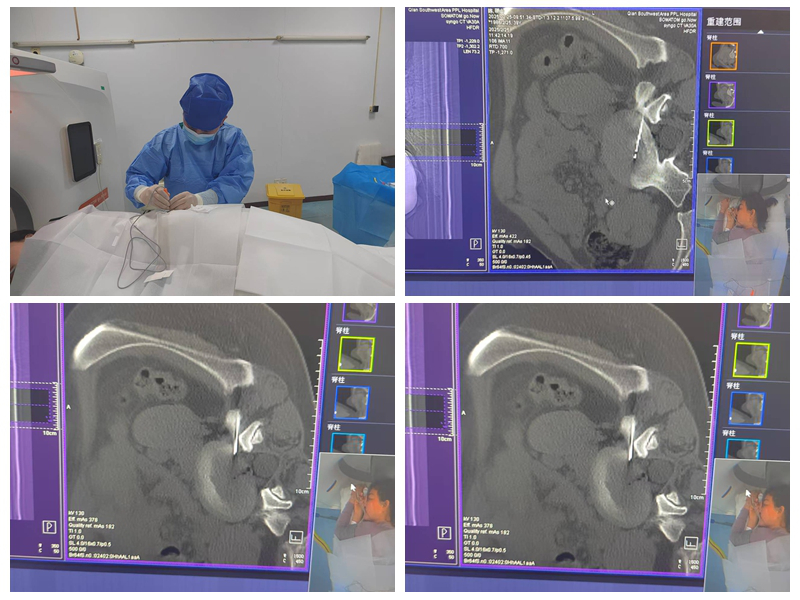

能完成该标准要求的绝大多数手术,包括选择性神经根阻滞技术、交感神经丛(干)介入医治技术、颅神经介入医治技术、神经射频调制技术、腰椎间盘介入医治技术、颈椎间盘介入医治技术、外周神经射频技术、脊髓电刺激、椎体成形术、硬膜外造影术、椎间盘造影术等。

选择性神经根阻滞技术

神经射频调制技术

腰椎间盘介入医治手术